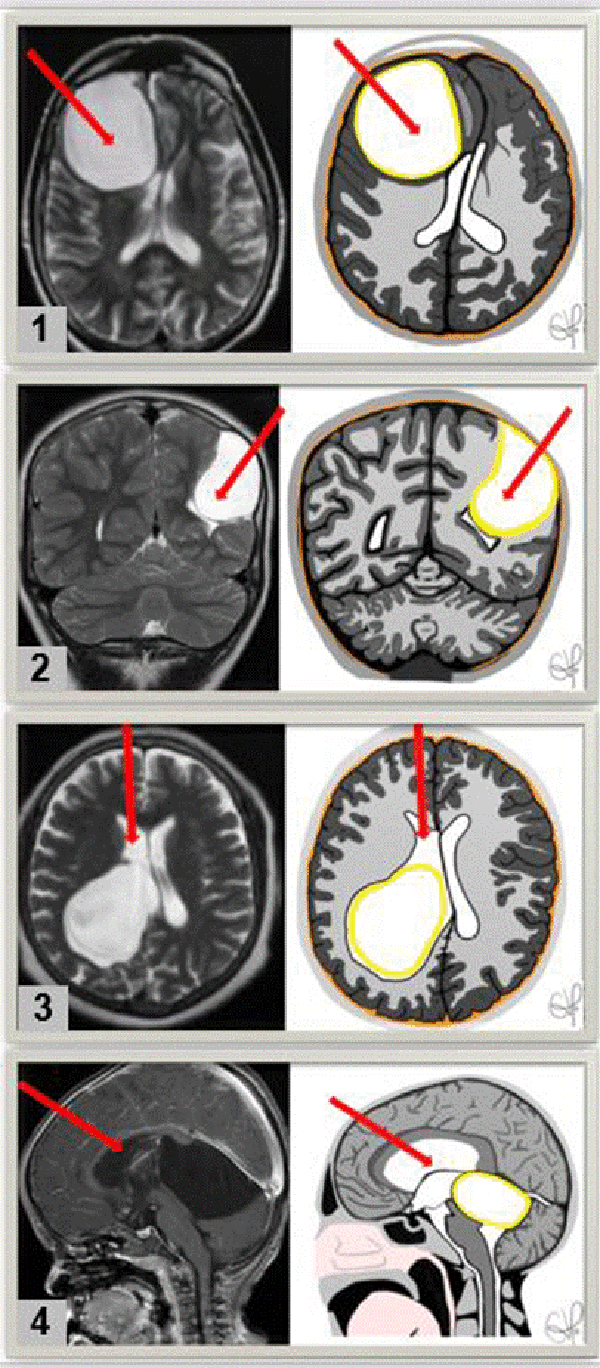

En los casos de los quistes intraventriculares o de la línea media, se ingresó a través del punto de Kocher derecho, teniendo en cuenta que el lado derecho es el hemisferio no dominante en la mayor parte de la población. Por otro lado, para aquellos quistes paraventriculares, el abordaje se realizó en el área más superficial del mismo, comunicándolo a la cavidad ventricular más próxima (Figura 1).

Figura 1: RMN (izquierda) y dibujo esquemático (derecha) que muestra las diferentes direcciones de los abordajes endoscópicos utilizados según la ubicación del quiste (Flecha roja). 1) vista axial de un quiste periventricular frontal derecho el cual desplaza línea media. Se plantea el abordaje al quiste desde la región más superficial para comunicarlo con la asta frontal del ventrículo derecho. 2) vista coronal de un quiste paraventricular parietal izquierdo en el cual se ingresa al quiste desde la región parietal y se comunica con el ventrículo izquierdo. 3) vista axial de un quiste intraventricular derecho, se realiza un abordaje precoronal ipsilateral, se ingresa al ventrículo lateral derecho y se realiza la fenestración del quiste. 4) vista sagital de un quiste ubicado en la cisterna cuadrigémina.